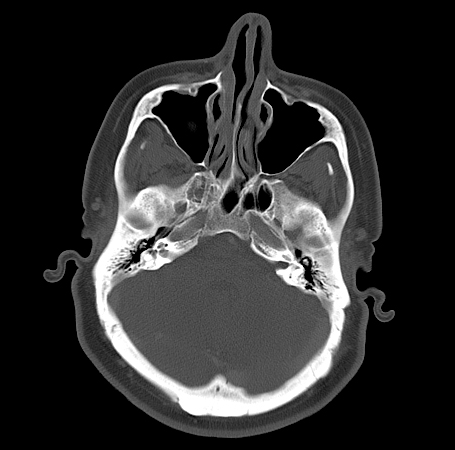

• Internal Acoustic Meatus